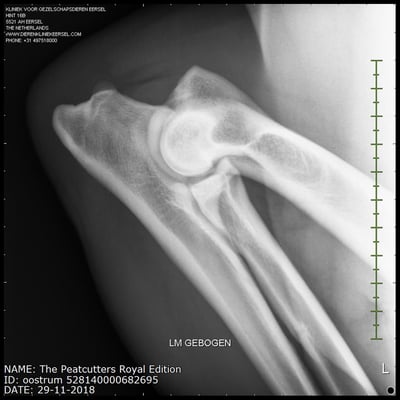

Sjors his official hip and elbow results with the photos. X-rayed at 20 months of age. HD-C, ED-0.